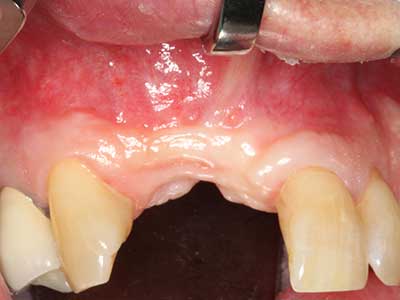

Piezosurgery has additional advantages when harvesting bone blocks. In addition to the high precision with osteotomy described above, the use of the thin saw tips specifically minimizes loss of material. Greater loss of material during harvesting can be expected with the thicker instrument tips, particularly when using Lindemann drills (Lakshmiganthan, Gokulanathan et al. 2012). The basal separation, which is necessary particularly for retromolar block transplants, is simplified by specially designed rectangular saws, with the result that piezosurgery is viewed as a precise, simple and safe procedure for harvesting retromolar bone blocks (Happe 2007) (Fig. 1-12).